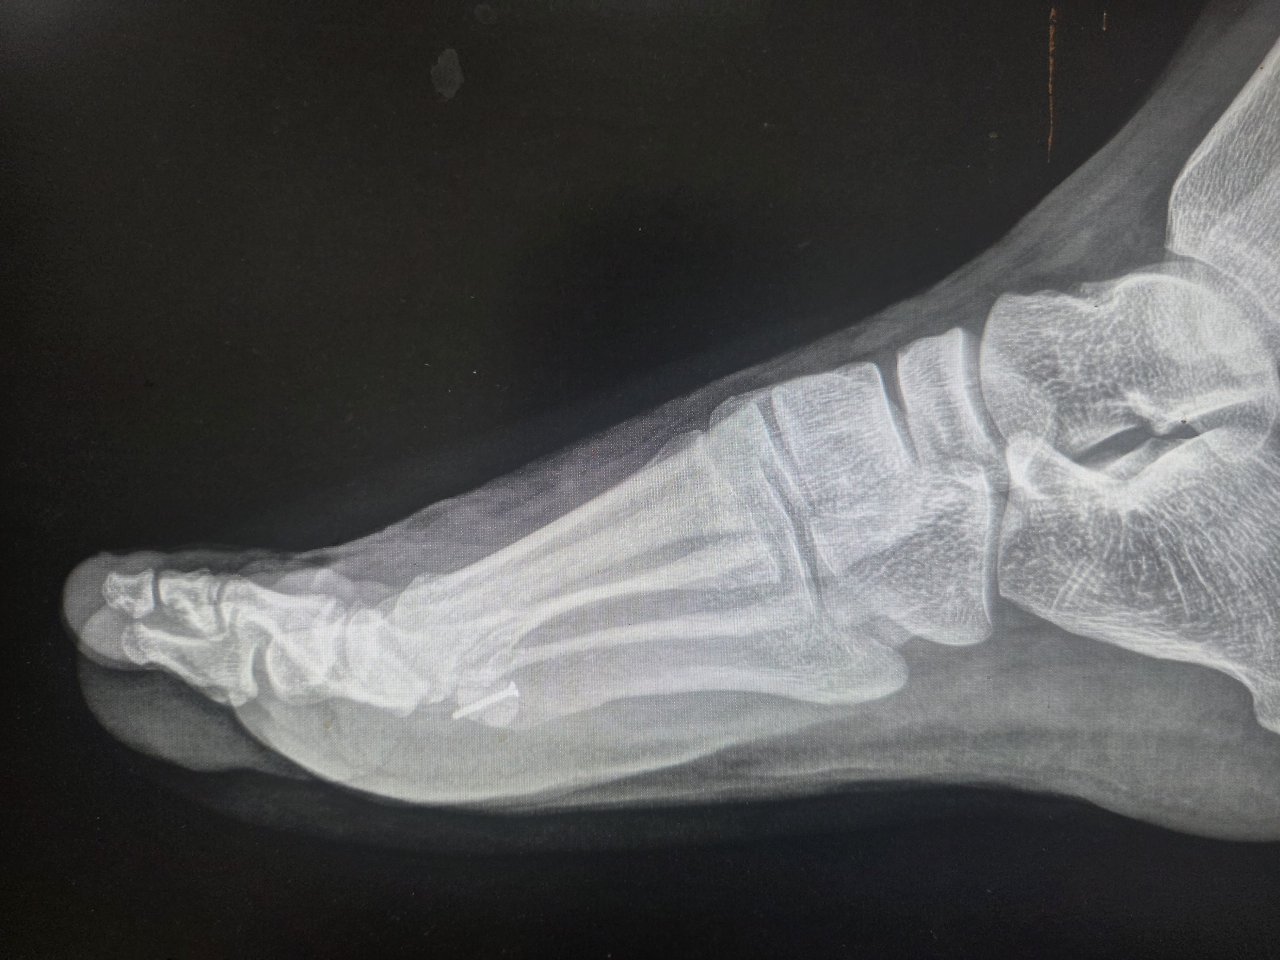

그가 처음 내 진료실을 찾은 것은 2024년 11월이었다. 당시 그는 이미 6개월 이상 엄지발가락 통증에 시달리며 여러 병원을 전전하던 상태였다. 깁스와 목발, 물리치료와 주사 치료까지 해볼 수 있는 건 다 해봤지만, 통증은 날카롭게 찢어지는 듯 심해졌고 보행조차 점차 어려워지고 있었다. 우선 시행한 X-ray 검사에서 통증 부위인 우측 종자골이 두 조각으로 나뉜 '이분 종자골' 형태가 확인되었다.

특이한 점이 있었다. 보통 이분 종자골은 80% 이상의 환자에서 양쪽 발 모두 관찰되는데, 이 환자는 유독 통증이 있는 우측에만 존재했다. 물론 한쪽만 이분 종자골인 경우도 드물지 않고, 환자의 직업 특성상 발에 충격이 잦아 '종자골염'일 가능성도 컸다.

하지만 증상이 계속 악화되고 있다는 점, 그리고 이분 종자골을 가진 사람도 사이 연골 결합이 손상되면 골절과 같은 양상의 통증을 느낄 수 있다는 점에 주목했다. 나는 환자에게 '종자골 골절'의 가능성을 설명하고 CT와 MRI 등 정밀 검사를 진행했다.